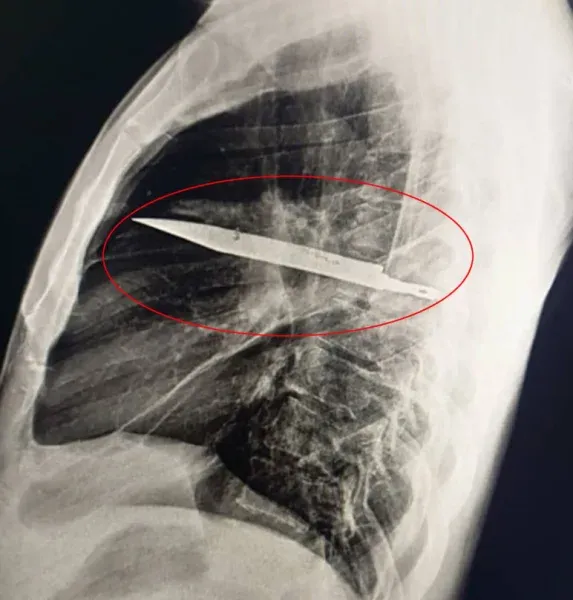

แพทย์ไม่สามารถหาสาเหตุของการติดเชื้อได้ จึงสั่งตรวจเอกซเรย์ และก็ต้องตกใจเมื่อพบใบมีดขนาดใหญ่ฝังอยู่ในหน้าอกของชายคนนั้น

จากภาพเอกซเรย์ด้านข้างทรวงอก พบวัตถุโลหะฝังอยู่ในส่วนกลางทรวงอก โดยมีลักษณะขุ่นทึบล้อมรอบ ซึ่งอาจเป็นเลือดที่คั่งค้างหรือเนื้อเยื่อพังผืดที่เกิดจากการบาดเจ็บเรื้อรัง

ใบมีดซึ่งทะลุเข้ามาทางกระดูกสะบักด้านขวาได้อย่างน่าอัศจรรย์ ได้หลบเลี่ยงอวัยวะสำคัญทั้งหมดไปได้ ในขณะที่เกิดเหตุการณ์เมื่อ 8 ปีก่อน โรงพยาบาลที่เขารักษาไม่มีเครื่องมือในการตรวจทางรังสี และเนื่องจากเขาไม่มีอาการเจ็บปวดหลังจากแผลหาย จึงไม่มีใครตรวจสอบเพิ่มเติม ที่น่าแปลกใจยิ่งกว่านั้นคือ ใบมีดไม่ได้ทำให้ผู้ป่วยวัย 44 ปี ผู้นี้รู้สึกไม่สบายเลยเป็นเวลานาน หนองที่ไหลออกมาเป็นผลมาจากเนื้อเยื่อที่ตายแล้วซึ่งสะสมอยู่รอบๆ วัตถุแปลกปลอม